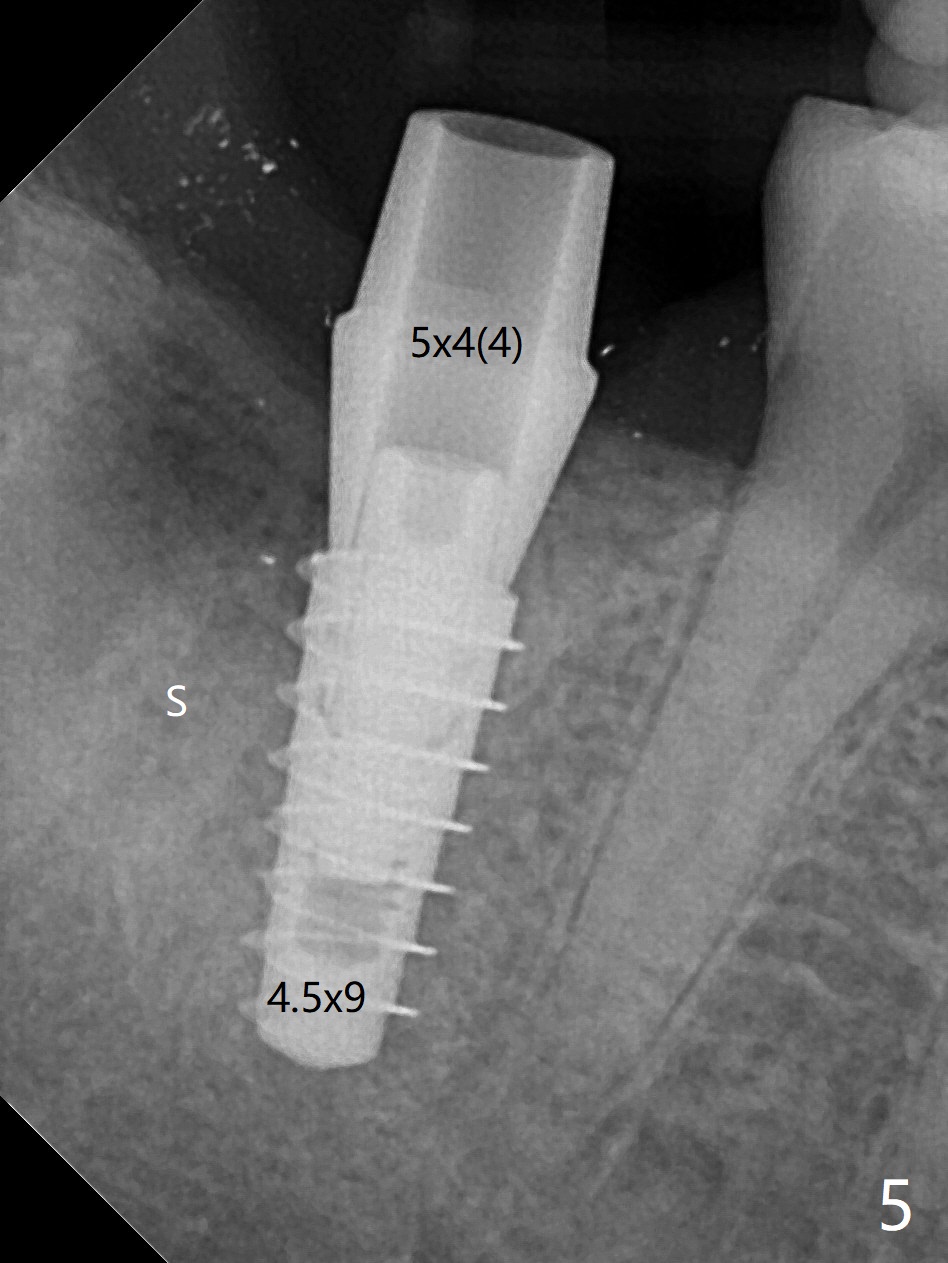

36岁女,右下第二磨牙颊侧瘘道,近中牙槽窝(图一:M)离下牙槽神经远,将是种植位点。图二是该牙CT3维横断面,显示近中(M),远中(D)牙根之间颊侧(L: 舌侧)连接(*);牙齿拔除后,牙槽窝成C型(图三,面对舌侧);由于颊侧骨板(图四:B)中断,缺损,植体将植入近中舌侧牙槽窝(绿色,导板)。优点便是三面骨质包绕(rao,图五),只有颊侧需要大量粘性骨粉(图六:*)。